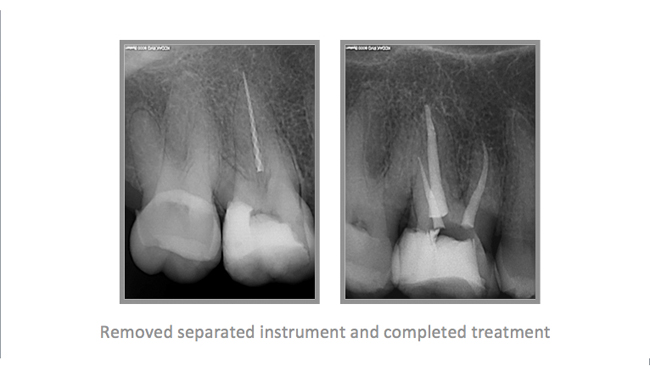

• A few Teeth Treated by Dr. Katsarsky

• A few Cases Treated by Dr. Katsarsky